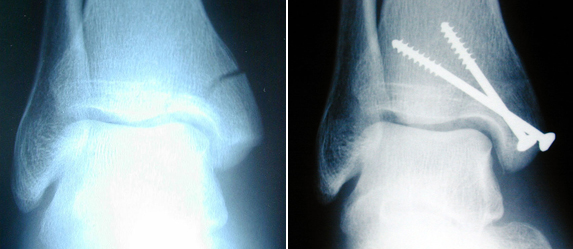

Well I broke my ankle 8 days ago and I am still waiting for surgery. I meet tomorrow with the surgeon to see if the swelling is down enough to do the surgery. I know they will be putting in metal plates and screws on both sides of my ankle. And I am not ready to sit and do nothing. So what I am asking is that anybody who has had this surgery how long before I can at least walk on it or even drive.

I broke my right ankle in 93. I have a plate & twelve screws in it. You can have them removed later but I didn't see the point in it.

I think I was in the boot for 8 weeks. I used to ride my bike with the boot for a little freedom.

Two screws in the right ankle after a freak rockclimbing incident at age 38. A week on the couch, no weight on it at all for a month, very gradual use after that, 6 months for full recovery. I first started putting weight back on it while in a swimming pool in chest-deep water, the buoyancy helped keep the stress low. Patience is the key, you'll need that ankle for the rest of your life!

I work for an orthopedic surgeon and have worked in ortho for almost 15 years. The ankle joint is complex so much depends on what was fractured (was it the lateral malleolus, calcaneus, distal fibula, distal tibia, talar dome or a combo of these?) as well as the type of fracture. There are also many types of fractures but I'm assuming you probably have a displaced comminuted fracture if you are having surgery. Your downtime also depends on your age, if you smoke and general overall health (diabetes etc) but what I've seen over the years is at least 3 months up to 6 months. An important part of recovery is physical therapy and following the recommendations of orthopedic surgeon as far as activity levels. If you try to do too much too soon you can actually do more damage on top of the traumatic damage to the joint and this will increase your healing time. Remember that your ankle joint supports the majority of the weight of your body. You'll probably be in a cast for a few weeks and then into a Cam walker or walking boot. Not sure if this helps and I wish you a speedy recovery.

Well its been 10 days since I broke my ankle and I am still waiting to have surgery. I see the doctor tomorrow afternoon and hopefully the can operate either Friday or Saturday. This has beed so frustrating for me. I am suppose to move in to our new House on Monday and I feel helpless as I can't left anything.

As for as my ankle goes I know they will be putting plates and screws on both sides. I think my skin is the only thing keeping my foot attached other the cast they keep putting on.